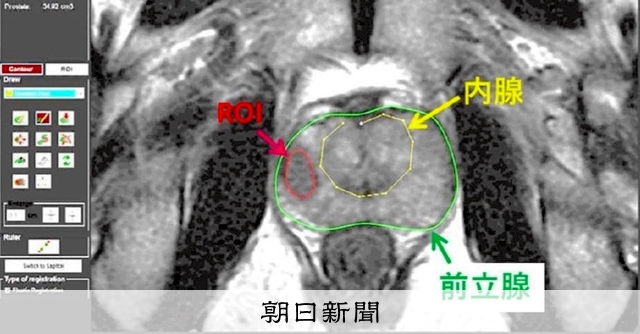

- CTスキャンやMRIなどの画像検査

- 前立腺を含む可能性のある、癌性であると考えられる組織の生検